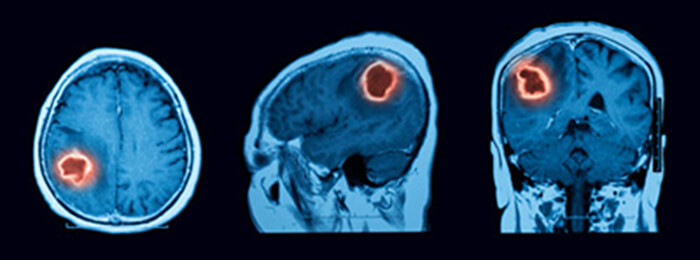

Oncology

The last clinical application that we will discuss is the case of a brain tumor. A brain tumor is a collection or mass of abnormal cells in your brain. They can be cancerous and malignant or non-cancerous and benign. Glioma is the most common malignant brain tumor which is a mass of abnormal cells that starts in the glial cells of the brain.

It is known that brain tumors are hyper vascularized, and characterized by a heightened blood Volume and hyper-permeability, thus, a Perfusion CT is performed (with or without a tracer which can provide additional physiologic and hemodynamic information) to provide quantitative information about cancer-related neovascularization that cannot be obtained by conventional imaging.

We have previously mentioned that Perfusion CT has an important role in the brain tumor detection and evaluation.

How does Perfusion CT provide information related to tumor growth?

It was proven that microvascular aggression is positively correlated with the aggression of tumors, whereas reduced permeability is associated with diminished tumor growth. This relationship can be demonstrated via perfusion imaging. To evaluate this permeability, microvascular density (MVD), microvascular cellular proliferation (MVCP) and permeability surface PS are measured.

CBF and CBV (perfusion CT measures) are correlated with MDV and MVCP, while PS has been found to be predictive of pathologic grade and well correlated with tumor mitotic activity. These findings suggest that perfusion maps of CBV, CBF, and PS serve radiologists as a means to guide biopsies. In addition, the higher levels of CBF, CBV, and PS may distinguish high-grade (grade III and IV) gliomas from low-grade (grade II) tumors.

Thus perfusion CT can be considered as a noninvasive imaging technique widely used for the evaluation of tumor grading, particularly in the case of high-grade gliomas. In short, perfusion CT has the capacity to provide hemodynamic information that is useful for tumor differentiation, tumor progression, and post treatment response. For many experts, perfusion CT is now considered a preferred imaging choice for brain tumor assessment and management.